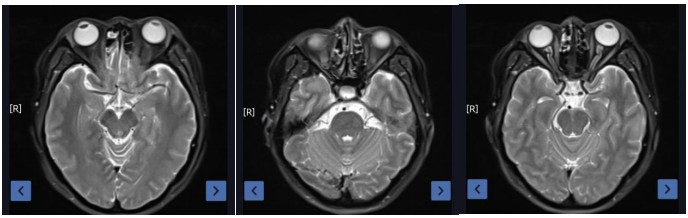

Figure 2: Post-treatment at 2 years (complete resolution of the lesion)

Results: The treatment was effective, with a partial response (PR) at the end of radiotherapy and 3 months post-treatment, and a complete response (CR) at 2 years post-treatment. The acute radiation skin injury grade was 1 according to RTOG criteria, and the adverse event grade was 1 according to CTCAE-V5.0. No ocular toxicity, such as vision loss or visual impairment, was observed 2 years after radiotherapy.

Clinical Outcome:The treatment was effective, with a partial response (PR) at the end of radiotherapy and 3 months post-treatment, and a complete response (CR) at 2 years post-treatment. The acute radiation skin injury grade was 1 according to RTOG criteria, and the adverse event grade was 1 according to CTCAE-V5.0. No ocular toxicity, such as vision loss or visual impairment, was observed 2 years after radiotherapy.